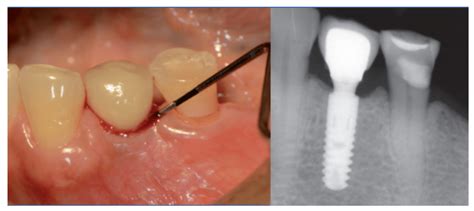

- Sangrado durante el sondaje: El sondaje es un procedimiento realizado por un dentista o periodoncista.

Si la mucositis no es atendida a tiempo, se forman las llamadas bolsas (o sacos) donde se acumula placa dental y restos de alimentos que son difíciles de eliminar con el cepillo de dientes o el hilo dental. En estos casos, solo una sesión de limpieza e higiene dental puede ayudar, ya que las bolsas pueden superar los 0,5 mm de profundidad.

Una vez comprobada la presencia de una periimplantitis en curso (mediante radiografías y sondeo gingival), se procede a una cuidadosa desinfección de la zona, liberándola de bacterias. Estos tratamientos funcionan muy bien en el caso de la periimplantitis en fase inicial (mucositis periimplantaria).